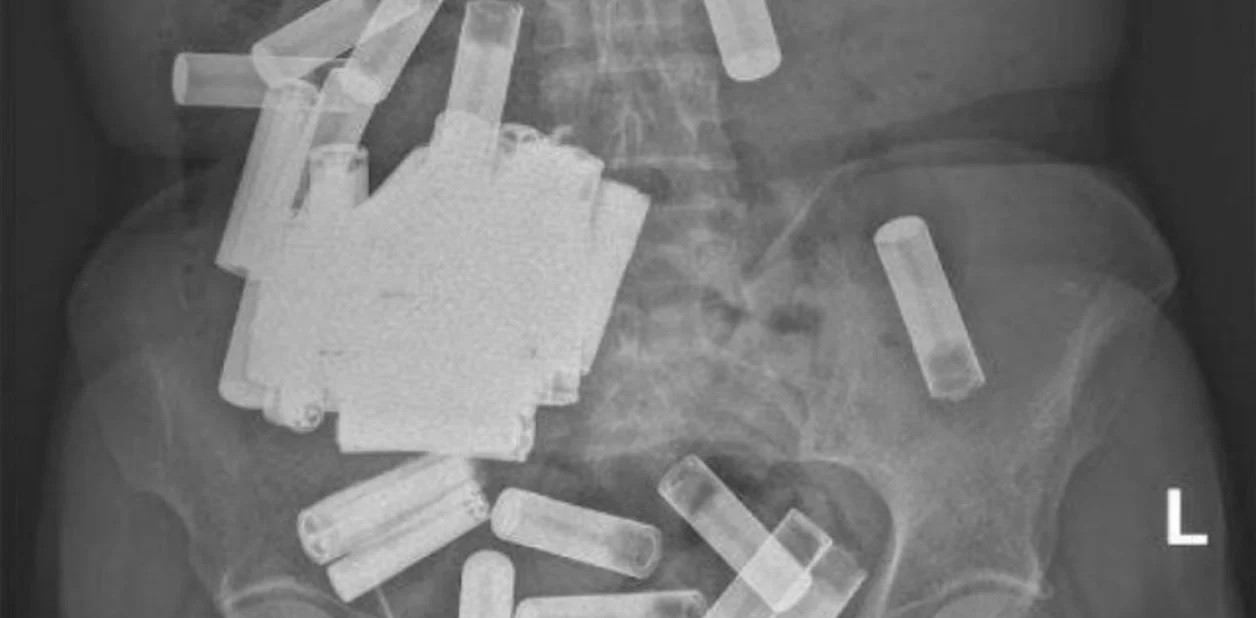

Una radiografía reveló una multitud de pilas en su abdomen, aunque afortunadamente ninguna parecía estar obstruyendo su tracto gastrointestinal (GI) y ninguna batería mostraba signos de daño estructural.

Por último, la exploración de rayos X confirmó que el tracto GI de la mujer estaba oficialmente libre de pilas y ella tuvo una "recuperación sin incidentes".